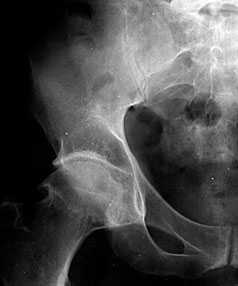

В начальных стадиях (1–2 стадии по Kellgren) ОА тазобедренных суставов при рентгенологическом исследовании определяются: незначительное сужение суставной щели, слабовыраженный субхондральный остеосклероз, точечные кальцификаты в области наружного края крыши вертлужной впадины (зачаток остеофитов), заострение краев ямки бедренной головки в области прикрепления круглой связки бедренной головки (рис. 1).

Рис. 1. Обзорная Rо-графия тазобедренного сустава в прямой проекции.

Деформирующий остеоартроз II ст. по Kollgren. Крупные остеофиты на краях суставных поверхностей. Грибовидная деформация бедренной головки